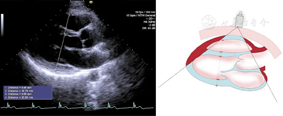

(3)胸骨旁主动脉短轴切面(图4图5图6)

胸骨旁主动脉瓣短轴切面和肺动脉长轴切面,显示舒张末期右心室流出道前后径、肺动脉瓣环内径、肺动脉主干内径和左右肺动脉主干内径测量方法,在肺动脉瓣瓣下2 cm处测量右心室流出道内径,在肺动脉瓣瓣上1 cm处测量肺动脉主干内径,在左右肺动脉主干起始处远心端1 cm处测量左右肺动脉主干内径